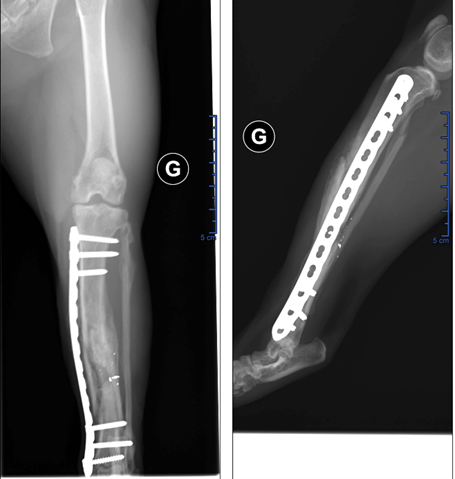

L’ostéosynthèse a débuté par un abord médial du membre pelvien, puis par le retrait des morceaux de plombs. Un rinçage abondant et la mise en place d’un clou centro-médulaire de faible diamètre par le foyer de fracture sont réalisés (figure 2). Un pansement de type Robert Jones est mis en place. Il sort sous amoxiciline et acide clavulanique (16,44 mg/kg BID pendant 15 jours) et meloxicam (0,1 mg/kg/J pendant 2 jours).

Figure 2 : Retrait de 2 plombs et mise en place d'un clou centro-médulaire

Figure 2 : Retrait de 2 plombs et mise en place d’un clou centro-médulaire